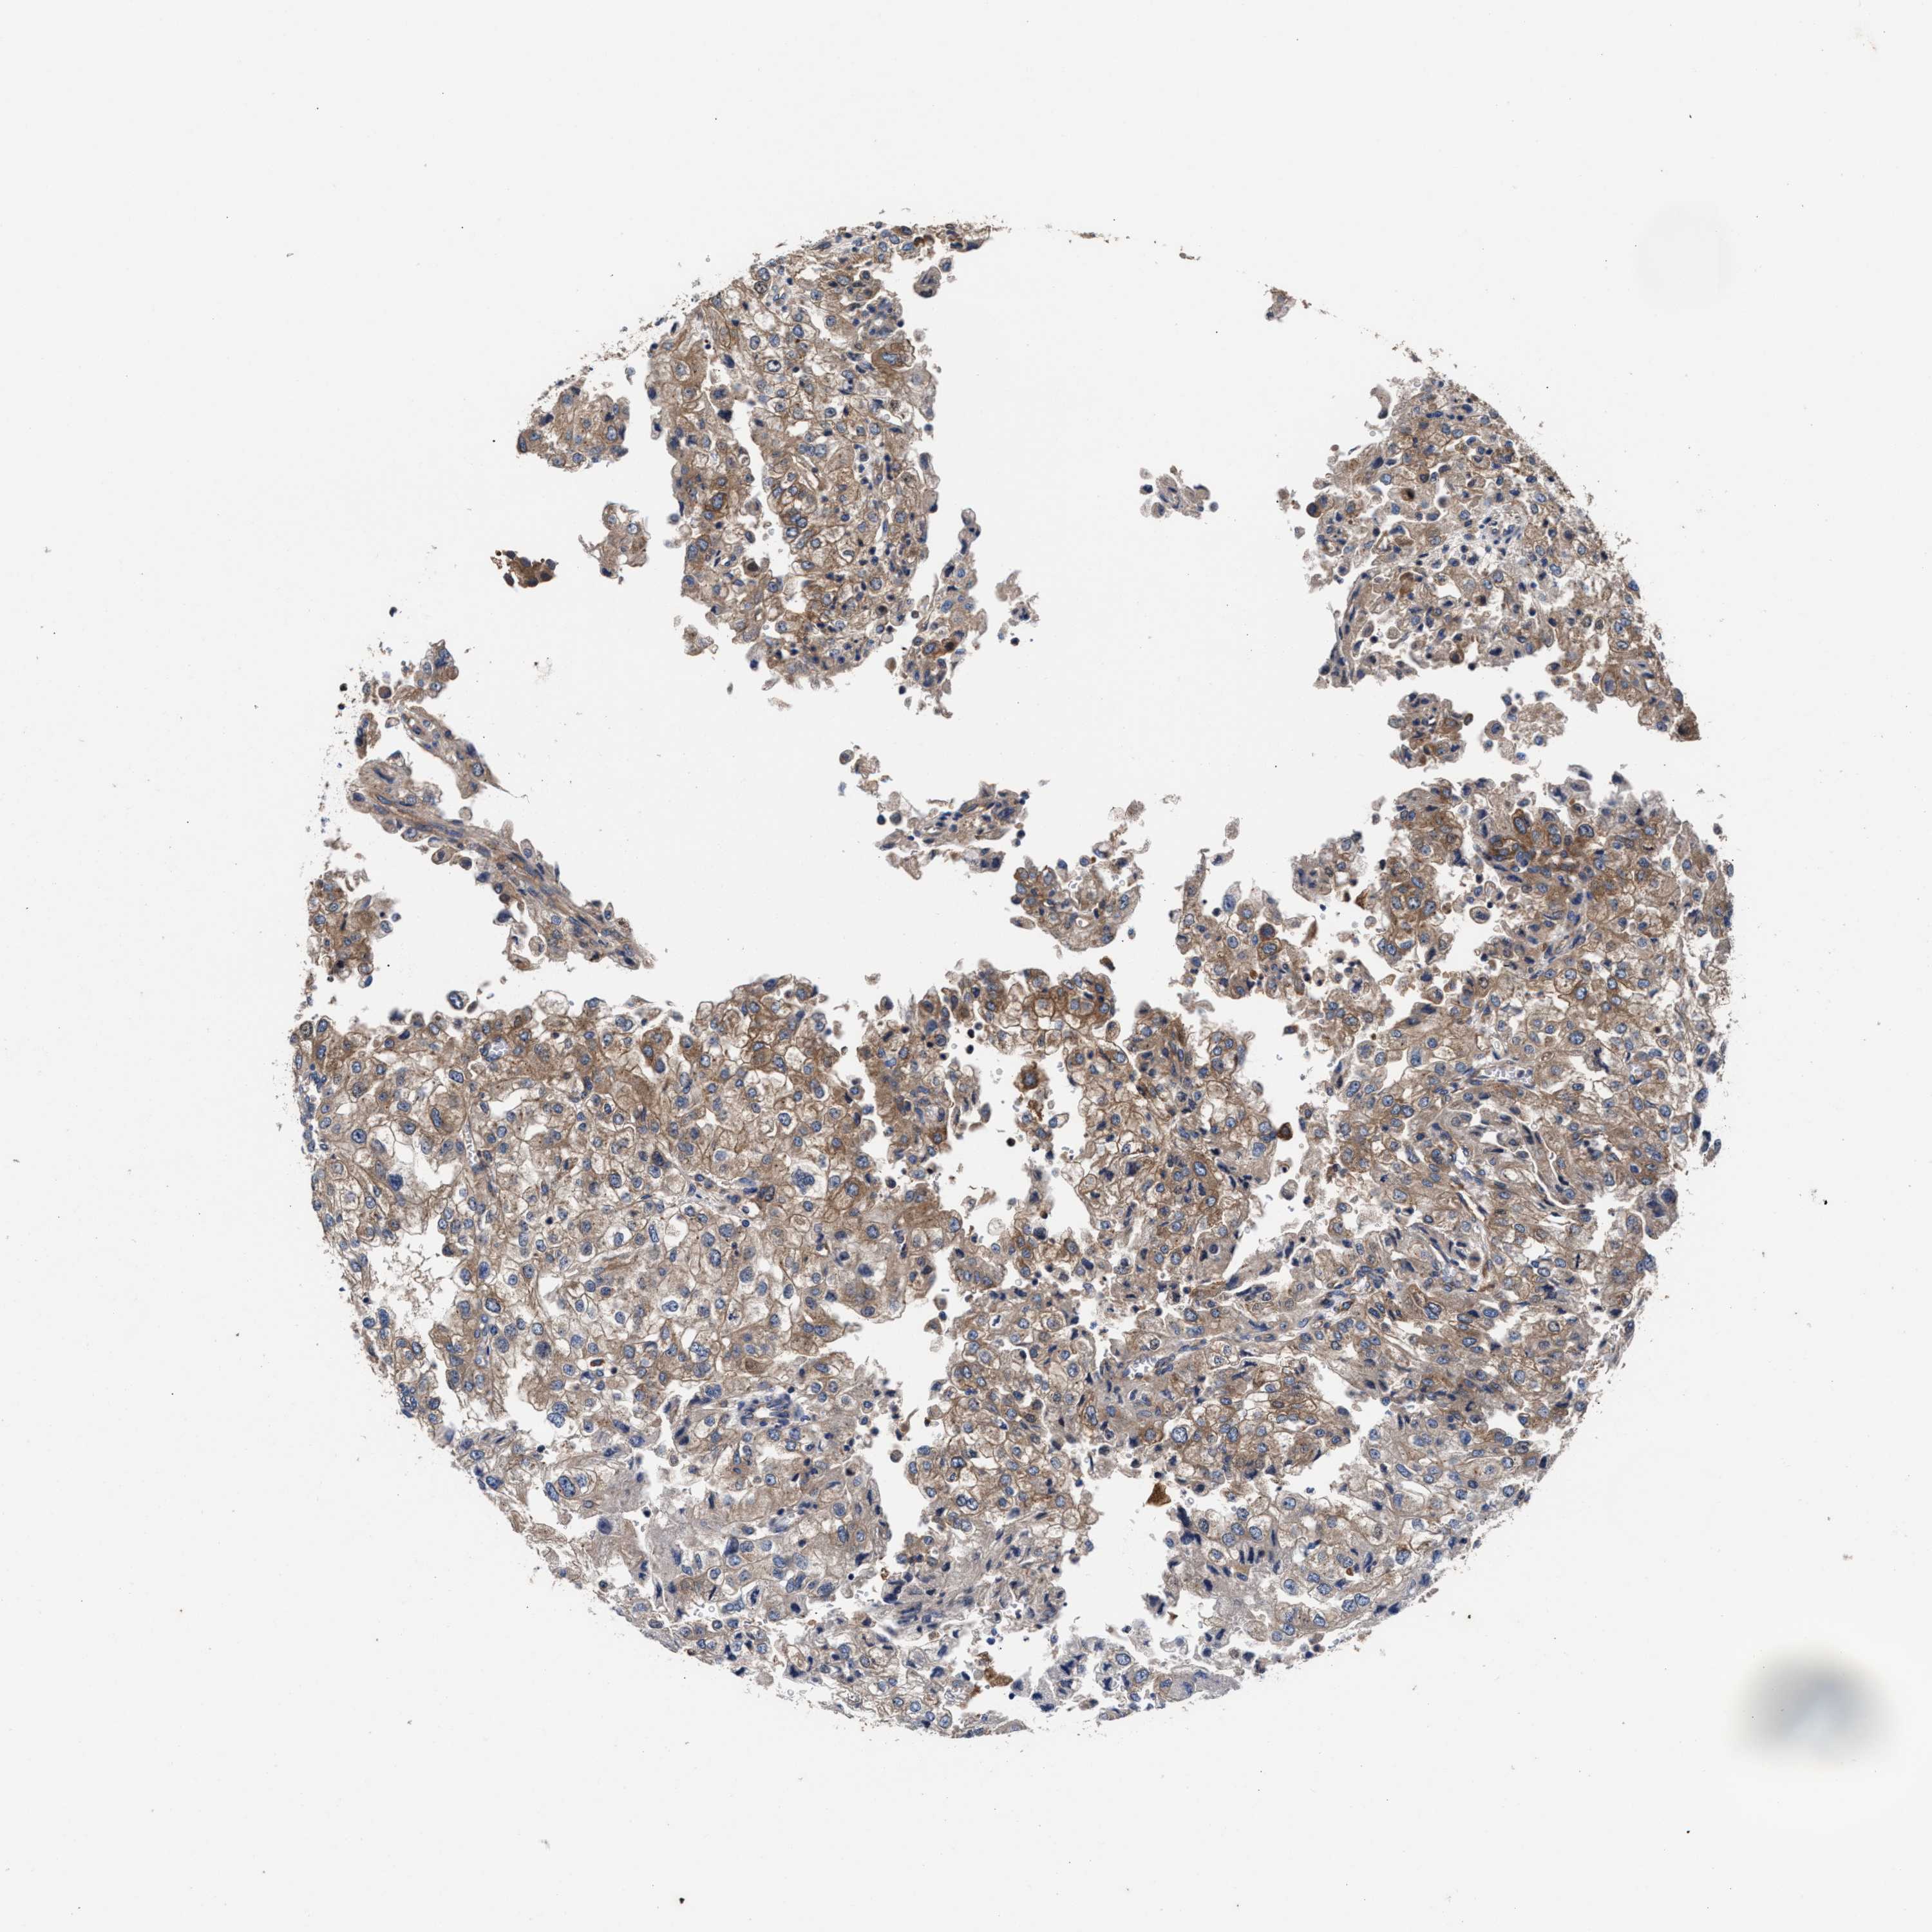

KIDNEY RENAL CLEAR CELL CARCINOMA (VALIDATION) - Interactive survival scatter ploti

The Survival Scatter plot shows the clinical status (i.e. dead or alive) for all individuals in the patient cohort, based on the same data that underlies the corresponding Kaplan-Meier plots. Patients that are alive at last time for follow-up are shown in blue and patients who have died during the study are shown in red.

The x-axis shows the expression levels (FPKM) of the investigated gene in the tumor tissue at the time of diagnosis. The y-axis shows the follow-up time after diagnosis (years). Both axes are complimented with kernel density curves demonstrating the data density over the axes. The top density plot shows the expression levels (FPKM) distribution among dead (red) and alive patients (blue). The right density plot shows the data density of the survived years of dead patients with high and low expression levels respectively, stratified using the cutoff indicated by the vertical dashed line through the Survival Scatter plot. This cutoff is automatically defined based on the FPKM cutoff that minimizes the p-score. The cutoff can be changed by dragging the vertical line or by entering a cutoff value in the square labeled "Current cut-off".

Under the Survival Scatter plot the p-score landscape (black curve; left axis) is shown together with dead median separation (red curve; right axis). Dead median separation is the difference in median mRNA expression between patients who have died with high and low expression, respectively. It is calculated as follows: median FPKM expression of dead patients with high expression - median FPKM expression of dead patients with low expression. This is intended to aid the user in visually exploring custom cutoffs and the associated p-scores and dead median separation.

Individual patient data is displayed and can be filtered by clicking on one or more of the category buttons on the top of the page. Categories describing expression level and patient information include: high, low, alive, dead, female, male and tumor stages. The scale of the x-axis can be toggled between linear and log-scale by clicking on the "x log" button. Mouse-over function shows TCGA ID, patient information and mRNA expression (FPKM) for each patient.

& Survival analysisi

Kaplan-Meier plots summarize results from analysis of correlation between mRNA expression level and patient survival. Patients were divided based on level of expression into one of the two groups "low" (under cut off) or "high" (over cut off). X-axis shows time for survival (years) and y-axis shows the probability of survival, where 1.0 corresponds to 100 percent.

SH3GL1 is not prognostic in Kidney Renal Clear Cell Carcinoma (validation)

Best expression cut offi

Based on the FPKM value of each gene, patients were classified into two groups and association between prognosis (survival) and gene expression (FPKM) was examined. The best expression cut-off refers the FPKM value that yields maximal difference with regard to survival between the two groups at the lowest log-rank P-value. Best expression cut-off was selected based on survival analysis .

When clicking on this number, the vertical dashed line indicating cut-off, the interactive survival plot, and the Kaplan-Meier curve will be adjusted to show results based on the best expression cut-off.

: 52.95

P scorei

Log-rank P value for Kaplan-Meier plot showing results from analysis of correlation between mRNA expression level and patient survival.

N/A

TCGA RNA samplesi

RNA-seq data is reported as average FPKM (number Fragments Per Kilobase of exon per Million reads), generated by the The Cancer Genome Atlas (TCGA) .

Normal distribution across the dataset is visualized with box plots, shown as median and 25th and 75th percentiles. Points are displayed as outliers if they are above or below 1.5 times the interquartile range. FPKM values of the individual samples are presented next to the box plot.

Average pTPM 61.9

Number of samples 100